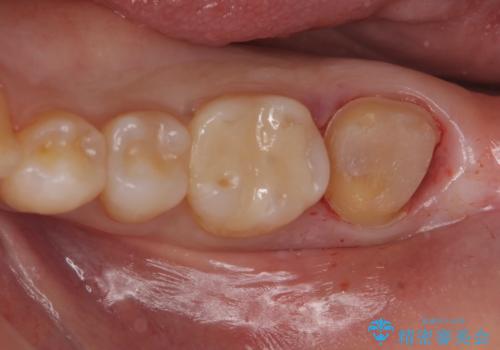

白い物で治療して欲しいとのことで、セラミックの詰め物だと詰め物の範囲が大きく、割れてしまう可能性があるので

ジルコニアクラウン(被せもの)で治療を行いました。

- 仮歯・ジルコニアクラウン 12.1万円費用は治療当時の料金となります